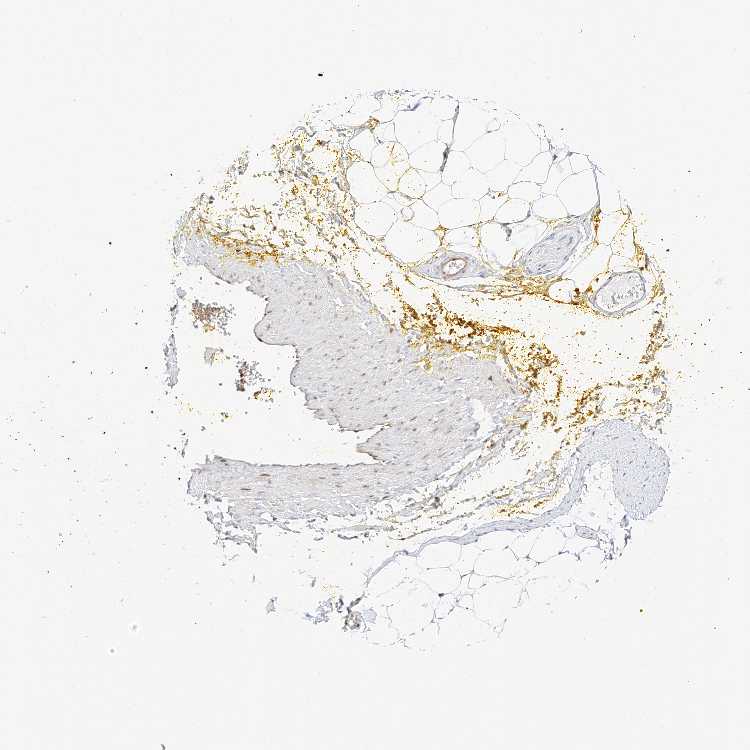

ADIPOSE TISSUE - Antibody stainingi

Antibody staining in the annotated cell types in the current human tissue is reported as not detected, low, medium, or high, based on conventional immunohistochemistry profiling in selected tissues. This score is based on the combination of the staining intensity and fraction of stained cells.

Each image is clickable and will lead to virtual microscopy that enables deeper exploration of all samples and also displays staining intensity scores, fraction scores and subcellular localization as well as patient and tissue information for each sample.

Antibody HPA028926

Adipocytes Medium